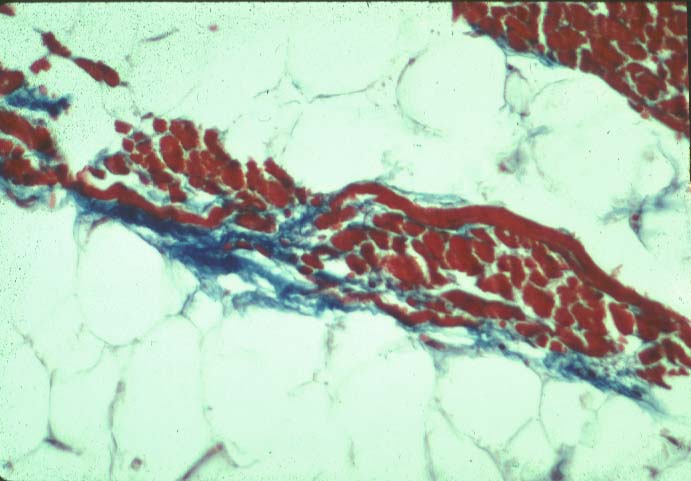

This is an interesting example of fibrofatty replacement of myocardium of the patient who died at night of Torsade de Pointe like with typical ARVD presented on top of this slide.

The top histologic document shows thin interstitial fibrosis bordering a strand of cardiomyocytes inside of major replacement of myocardium by fatty tissue.

1. Fibrosis is located on one side of the surviving fiber.

2. There is no fibrosis inside fatty tissue

This suggests that fibrosis is a secondary phenomenon occuring after fatty transformation